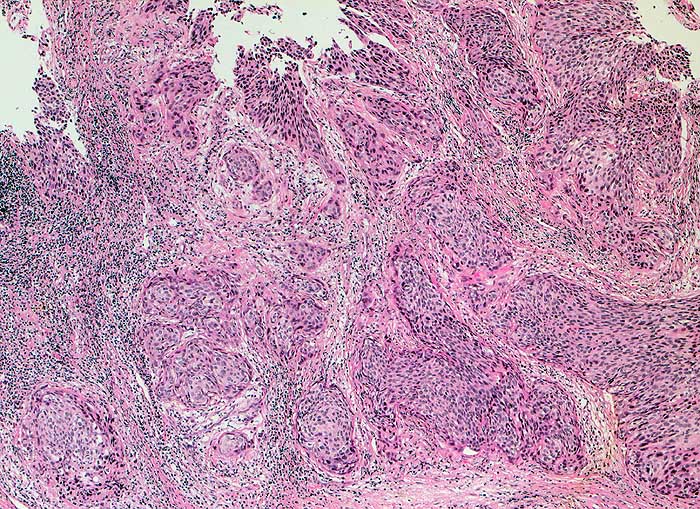

Plattenepithelkarzinom der Zervix

Die Tumorzellen liegen einzeln oder in kleinen Verbänden und ganzen Gewebsfragmenten. Die polymorphen Kerne sind vergrössert und enthalten verklumptes unregelmässig verteiltes Chromatin und grosse Nukleolen. Gut differenzierte Karzinome erkennt man am breiten und oft verhornten Zytoplasma. Längliche bis fadenförmige Tumorzellen mit pyknotischen Kernen können als einziger Hinweis auf das Vorliegen eines Karzinoms vorhanden sein. Wenig differenzierte Karzinome haben polymorphe und schlechter erhaltene Kerne. Der Hintergrund ist meist detritisch und oft hämorrhagisch. Ulzeration, Einblutungen und bakterielle Infektionen beeinflussen den Erhaltungszustand und die Art der abgestrichenen Zellen. Ist die Oberfläche eines ulzerierten Karzinoms von einem Fibrinschorf bedeckt, enthalten die Ausstriche lediglich Detritus, Granulozyten und Erythrozyten, aber keine Tumorzellen. Die Sensitivität für die Karzinomdiagnose ist aus diesem Grund geringer als für die Diagnose eines Carcinoma in situ.